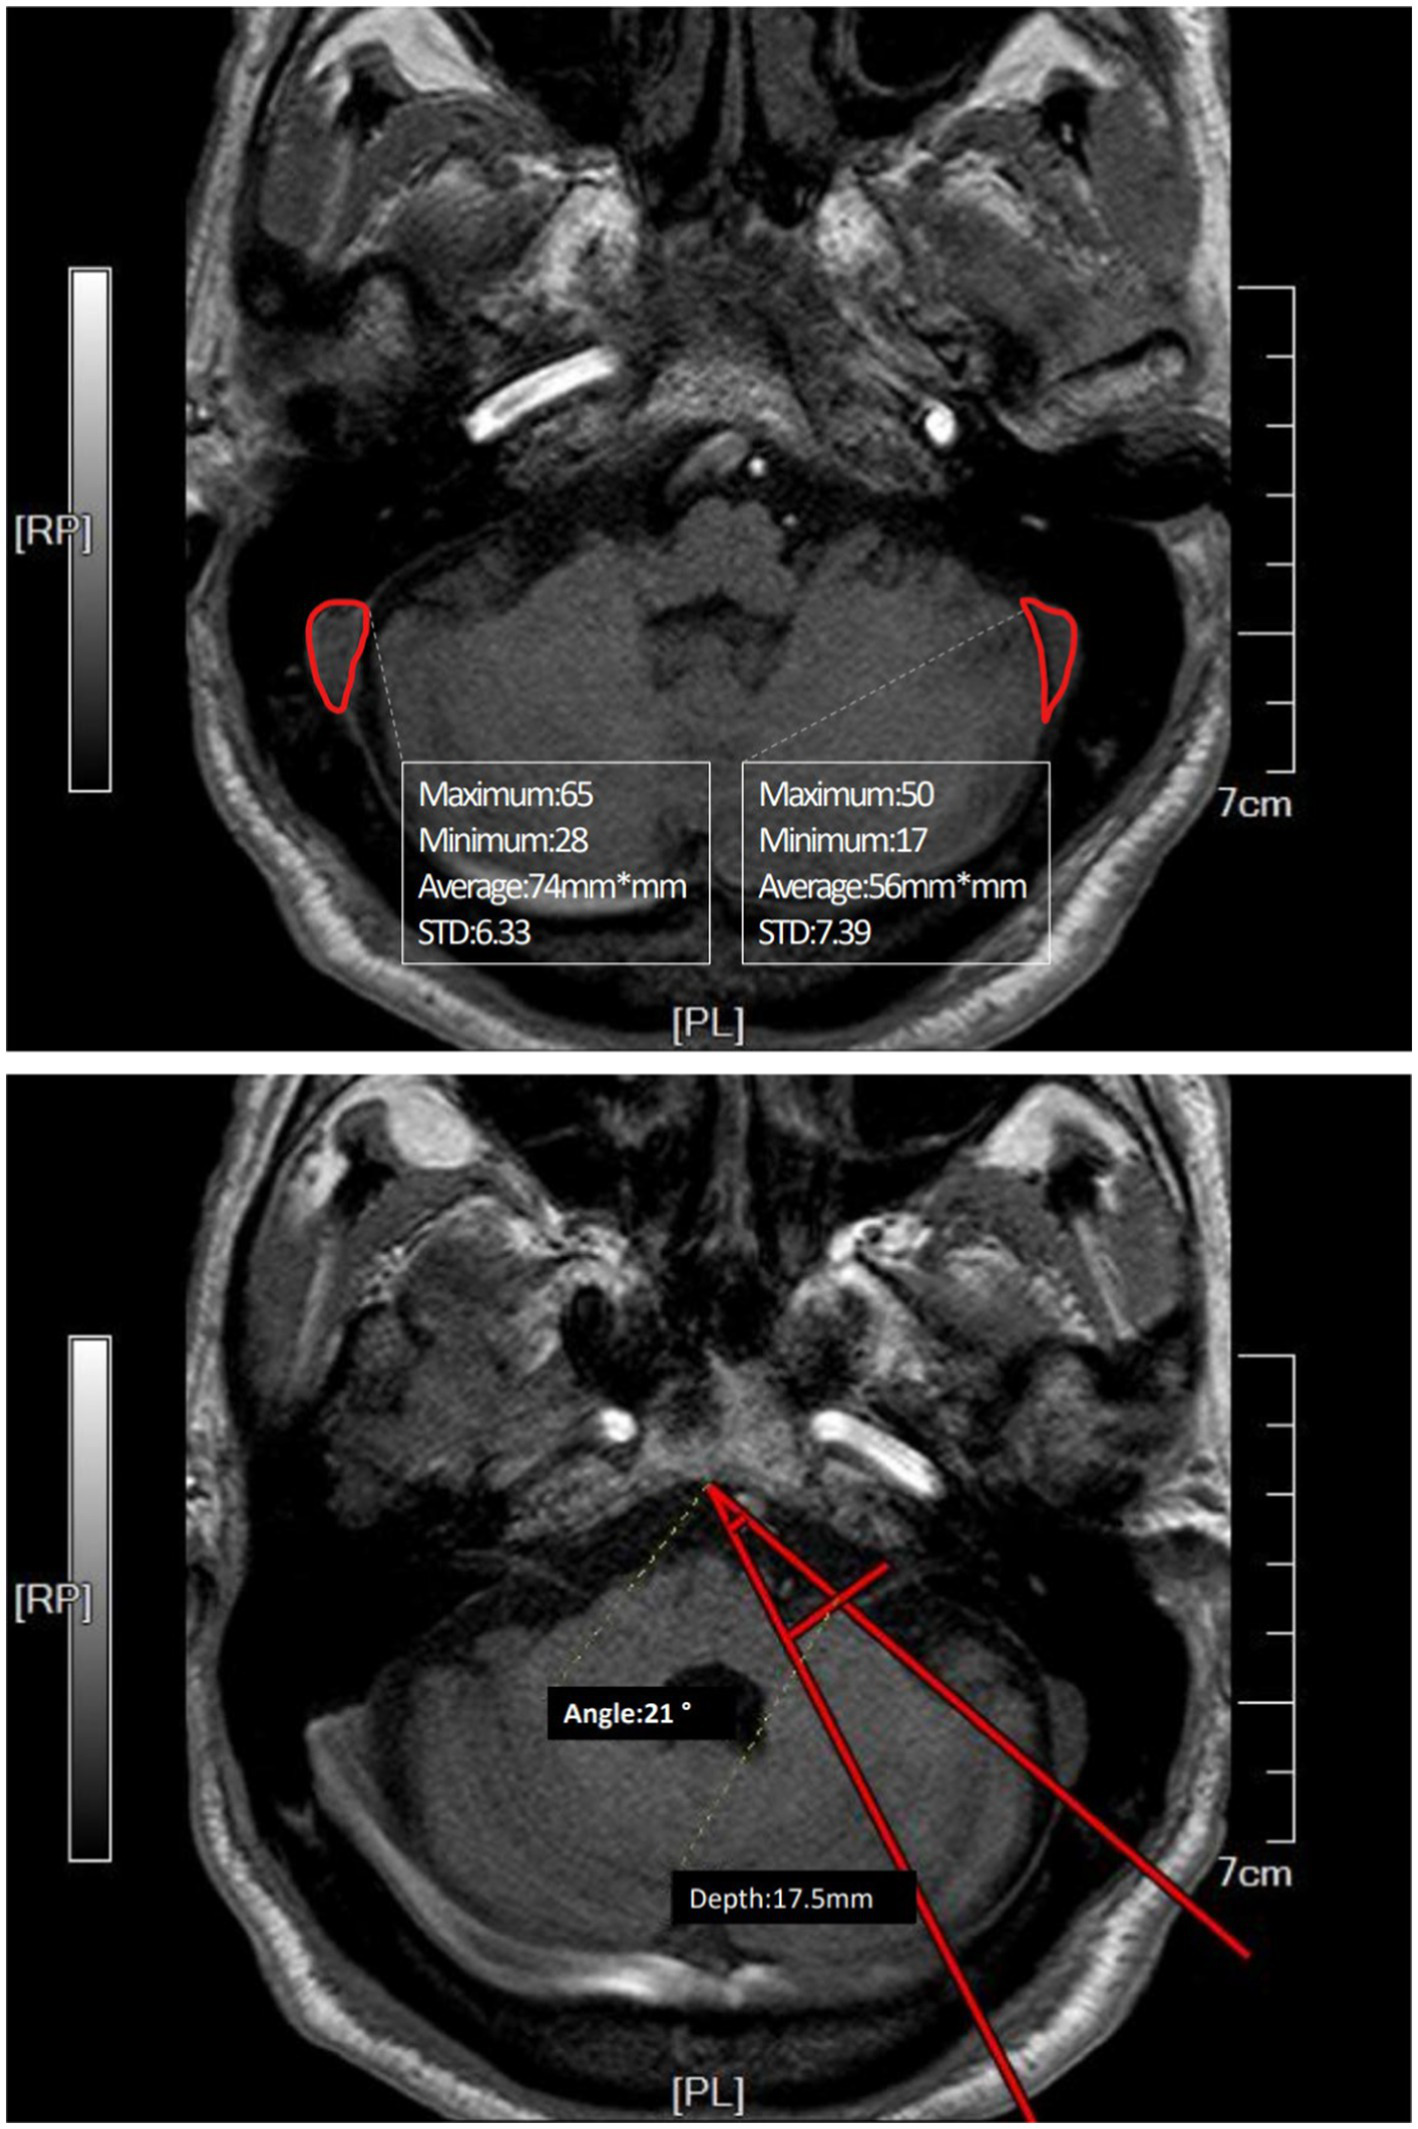

The difference between the two groups was not statistically significant, given the limited sample size, but the advantage of the improved method based on these differences was evident. Planning the line of incision carefully based on different sizes and angles of sinuses achieved satisfactory surgical view. Intraoperative adjustments of bone flaps due to sinus protection were avoided. Figure 2 shows the preoperative planning MRI image of an improved MVD surgery implementing the improved method. The position and skull thickness of the sigmoid sinus were determined by MRI. The surgical approach for the same case during the surgery is shown in Figure 3, where a bone window is opened to reach the responsible blood vessels, revealing the sigmoid sinus during surgery. The postoperative CT of this case (Figure 4) showed that the bone flap was returned right next to the sinus edge. This way, the risk of damaging venous sinuses was reduced and bone window exposure was improved, offering good surgical fields.

Figure 2

Preoperative MRI image of a case where the affected side and the dominant side are ipsilateral (right side). The area of the sinus was measured in the plane of REZ (root entry zone) where the root of the facial nerve is located. The angle was measured by connecting the midpoint of the REZ plane slope and the sinus border to the responsible blood vessel at its deepest point. The distance from the responsible blood vessel’s deepest point to the perpendicular line from the deepest point of the angle to the petrous bone wall was the depth of the responsible blood vessel.